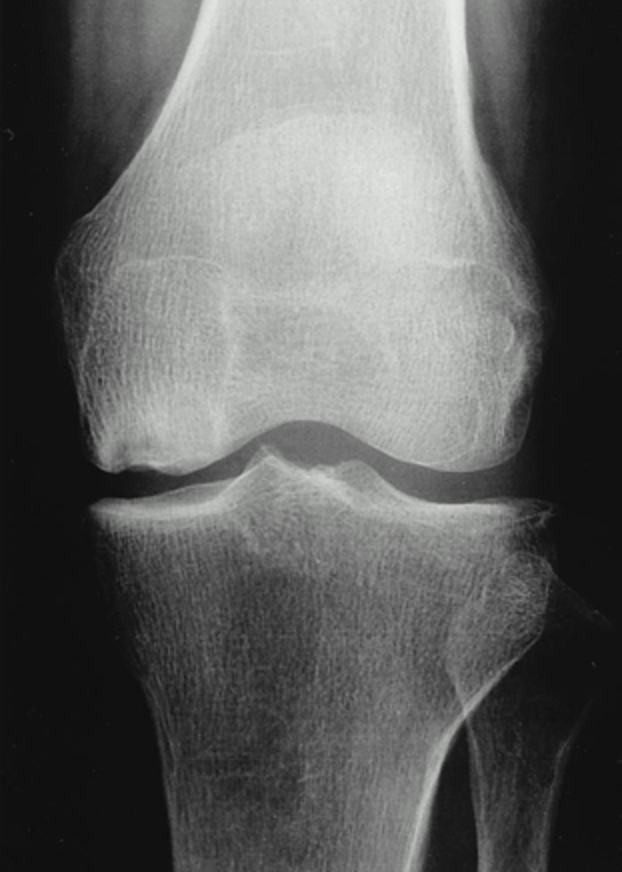

After a comprehensive history has been taken and physical examination performed imaging is the next step. In the early course of the disease, the radiographs are normal. In the later stage of the disease x rays of the knee will show flattening of the involved condyles (fig 1).

Fig 1.